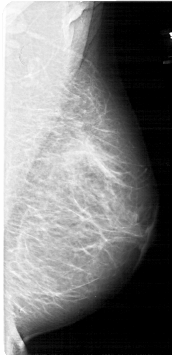

A_1982_1.RIGHT_MLO

RIGHT_MLO LINES 5311 PIXELS_PER_LINE 2566 BITS_PER_PIXEL 12 RESOLUTION 43.5 NON_OVERLAY